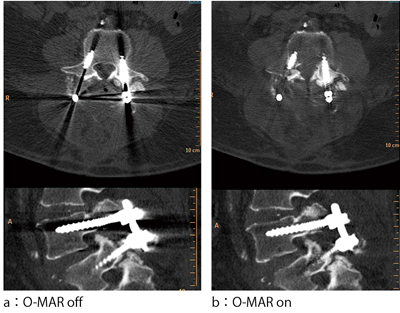

O-MARは,整形外科領域での金属インプラントを対象とした再構成技術であり,大きく期待される領域としては,人工股関節形成術や後方椎体間固定術などの術後フォローアップCTにおいて,周辺構造物である骨癒合などの評価や(図5),整形外科以外のオーダにおいても,金属アーチファクトのために目的部位の観察が困難な症例すべてに有効だと考える。ほかにもニーズの高い領域としては頸部CTA検査が挙げられ,口腔インプラントのアーチファクトによる血管の欠損を防ぐ効果が期待できる(図6)。

![]() 図5 後方椎体間固定術画像 |